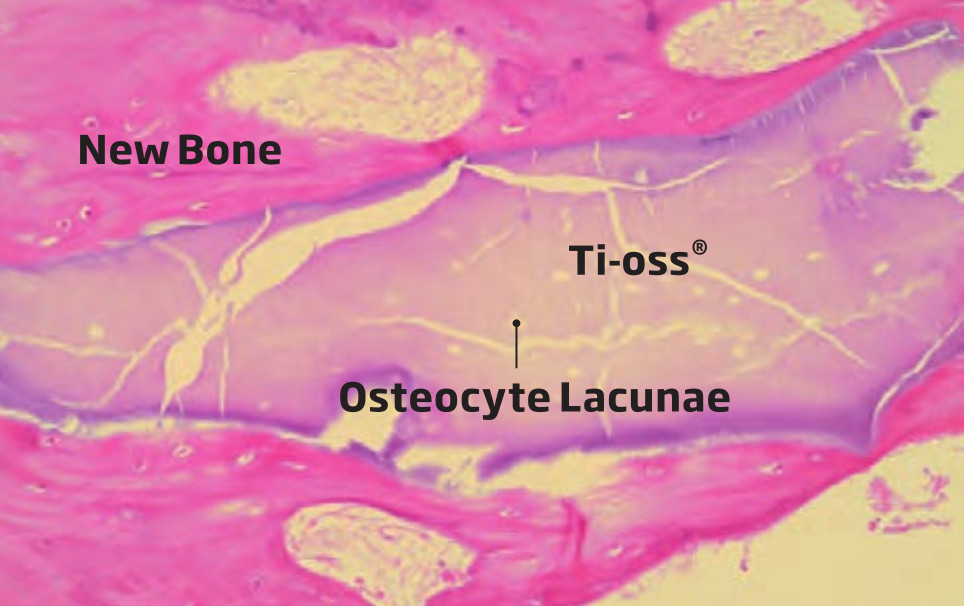

Osteoprzewodzący charakter powierzchni Ti-oss® oceniono na podstawie próbek biopsyjnych.

Konsekwentne tworzenie się nowej tkanki odnotowano w kilku różnych przypadkach klinicznych, dzięki czemu jesteśmy w stanie osiągnąć, przewidywalność i niezawodność procesu regeneracji we wczesnych etapach tworzenie się nowych struktur.

Obserwacja Osteocyte Lacunae

Research Report date: May, 2012 • Kim, Sun Young, D.D.S. Prosthodontist • Suplant Dental ClinicSeoul, Korea

Wyniki biopsji po 4 miesiącach